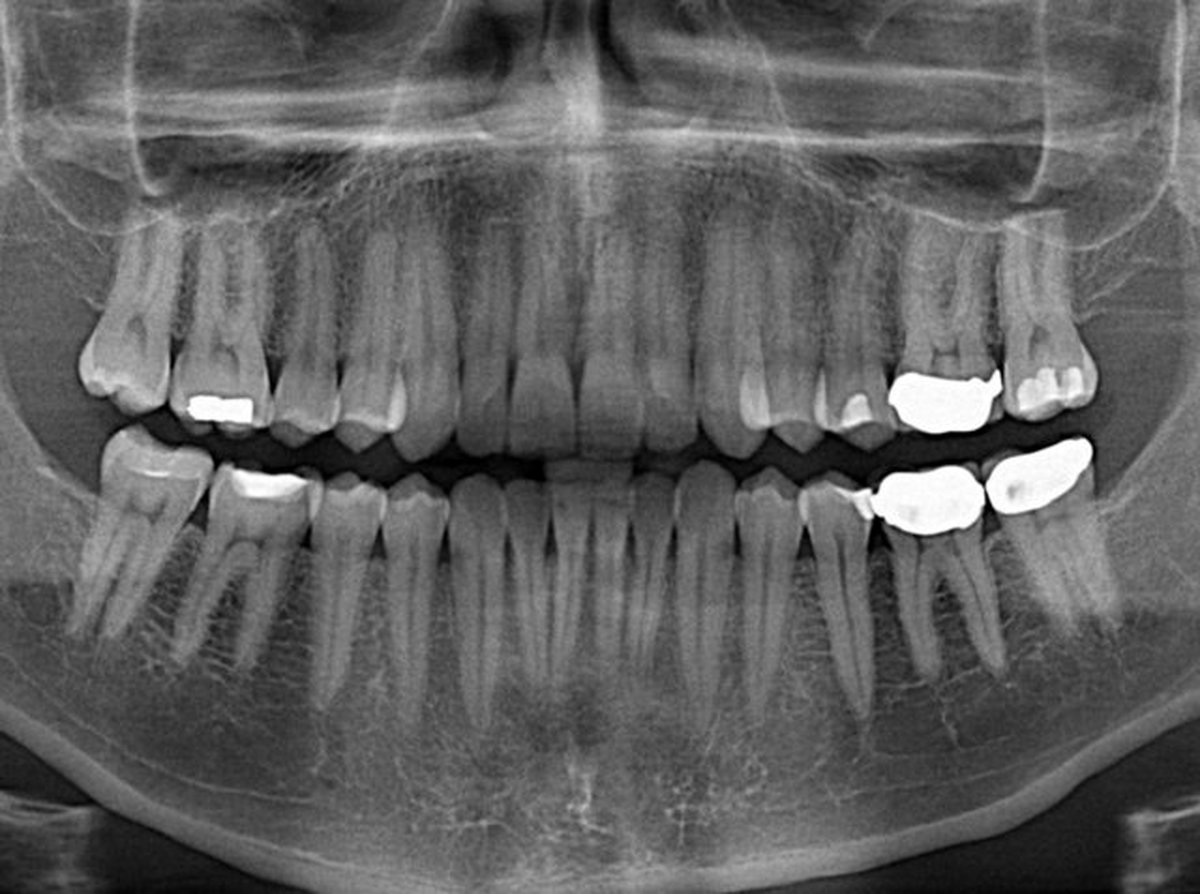

رییس هفدهمین همایش سالانه انجمن متخصصان دندانپزشکی ترمیمی و و زیبایی ایران با اشاره به اینکه بعد از سرماخوردگی، پوسیدگی دندان دومین بیماری عفونی قرن و یکی از شایعترین بیماریهای عفونی در کشورهای جهان سوم به شمار میرود، گفت: رسانهها در افزایش آگاهی مردم در بهداشت دهان و دندانها نقش مهمی دارند.

استاد دانشگاه علوم پزشکی شهید بهشتی عنوان کرد: از آنجایی که بیشترین مراجعه کننده برای درمان در مطبهای دندانپزشکی در حیطه پوسیدگی است، این موضوع بسیار مهم و حائز اهمیت است.

وی گفت: پوسیدگی دندانی هنوز درصد زیادی از مردم را درگیر خود کرده و علیرغم تلاشهایی که در ایران انجام شده، اما آمار پوسیدگی دندانها بالا رفته و باید با استفاده از ابزارهای علمی بتوانیم به مقابله با پوسیدگی برآییم.